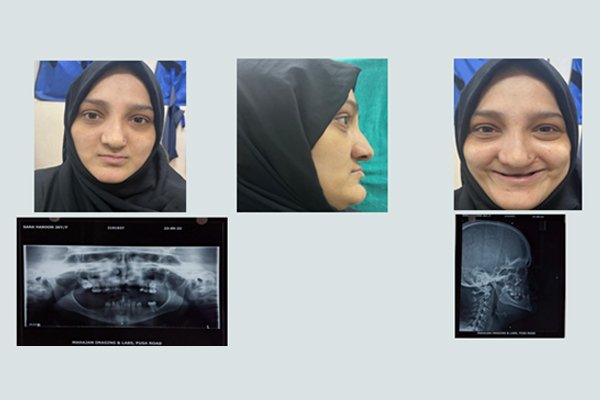

The Patients With clefts Presents a Complex biologic, Sociologic and Psychologic Problem,

One Whose best Management Involves Several Disciplines.

Cosmetic abnormality which affects the patient’s self esteem Difficulties with feeding the new born baby and eating solids later.

Coping With the Challenges of this medical condition.

Ideal treatment is 3-6 months for cleft lip patients and 9-18 months for cleft palate Patients.

Surgical treatment called palatoplasty and Cheiloplasty are carried out on babies from the age of 3 month to 12 months [ Uk ], 6-14 month [ USA ], EU 3-17 Months and India 3-18 Months.

Success rate 68.8-70%

Average surgical costs between E2,419 -E4,032 in India , Uk – NHS based E150, USA – Insurance claim , EU $10,000-E-$13000 [ State health Insurance ].